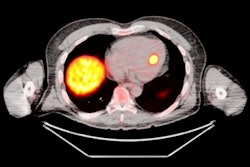

The researchers performed automated body composition analysis on 74 consecutive GEP-NET patients who had received whole-body gallium-68 (Ga-68) DOTATOC PET/CT exams as well as BIA and DEXA scans between February 2019 and October 2021. The deep-learning model was applied to the contrast-enhanced, 5-mm, whole-body CT images for all 74 patients.

The model examined seven volumes for different body compartments and quantified subcutaneous adipose tissue, visceral adipose tissue, intermuscular adipose tissue, epicardial adipose tissue, and paracardial adipose tissue. Muscular and bone tissue volumes were computed to generate a skeletal muscle ratio and body fat ratio.